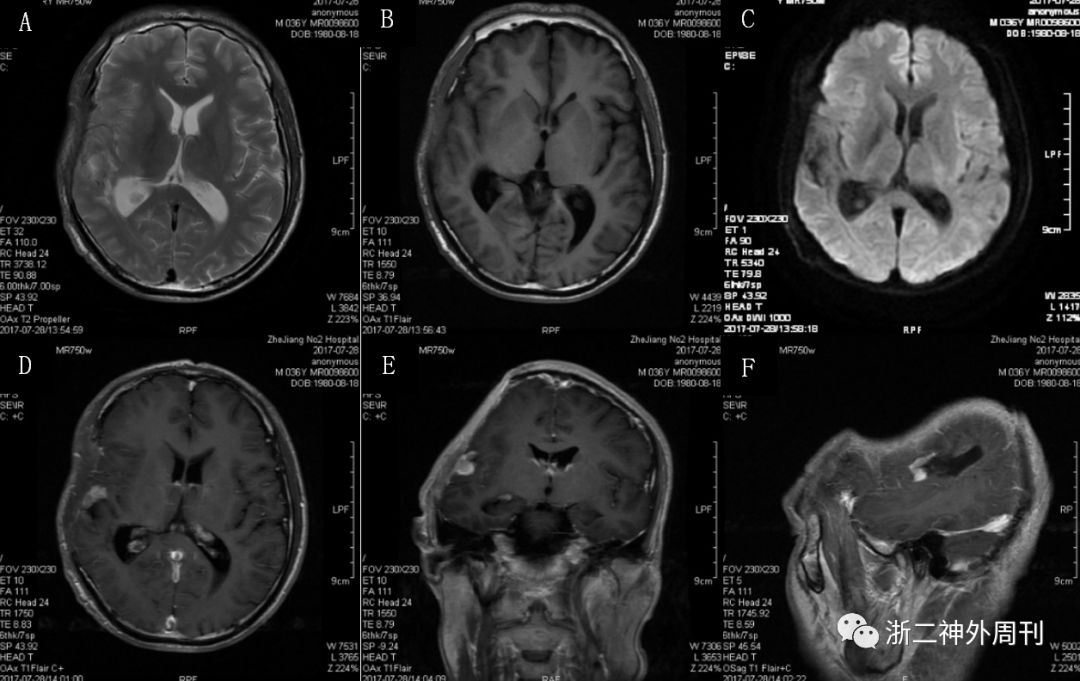

2017-06-20开始行放疗:右颞叶残留灶及周围高危区PTV1 48Gy/24F + PGTV 10Gy/5F,泰道每日75mg/m2 同步化疗。放疗结束后予泰道5/28方案化疗6周期(第1周期150 mg/m2/日,第2-6周期200 mg/m2/日)。放疗结束后头颅MRI复查无明显变化,至放疗后1月开始病灶缩小,放疗后3月明显缩小,放疗后5月可见病灶已消失(图3,4)

图3.放疗结束复查头颅MRI示术后残腔边缘异常强化灶同放疗前无明显变